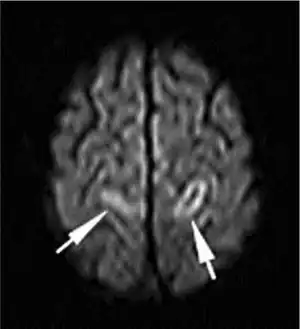

Venous thrombosis is blockage of a vein caused by a blood clot. Forms include deep vein thrombosis (DVT), when a blood clot forms in a deep vein. If a thrombus breaks off (embolizes) and flows to the lungs to lodge there, it becomes a pulmonary embolism (PE), a blood clot in the lungs. The conditions of DVT only, DVT with PE, and PE only, are all captured by the term venous thromboembolism (VTE).[2]

Less common forms of venous thrombosis exist; some of these can also lead to pulmonary embolism. Venous thromboembolism and superficial vein thrombosis account for about 90% of venous thrombosis. Other rarer forms include retinal vein thrombosis, mesenteric vein thrombosis (affecting veins draining blood from the gastrointestinal organs), cerebral venous sinus thrombosis, renal vein thrombosis, and ovarian vein thrombosis.[3]

- Cerebral venous sinus thrombosis, cavernous sinus thrombosis and jugular vein thrombosis: thrombosis of the veins of the brain and head